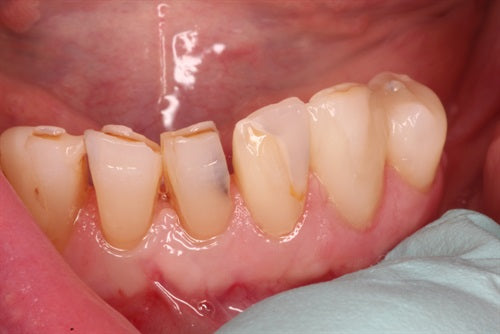

Composite repair for uneven incisal wear

Posted on October 19 2022

Introduction: Patient did not like the unevenness of his front teeth. Upon close examination, I observed both #'s 8 & 9 have a palatal inclination. I can now add composite... Read More